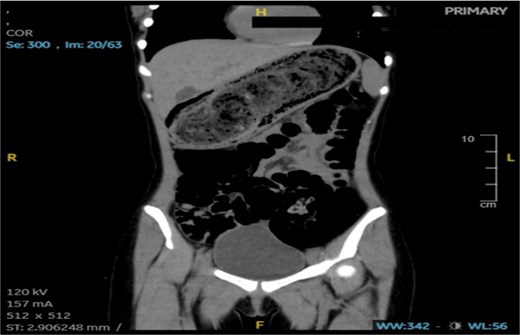

An abdominal CT scan showed a large, intragastric mass with a characteristic mottled appearance and gas entrapment (Figs 1 and 2), consistent with a trichobezoar. The mass extended into the duodenum, confirming the diagnosis of Rapunzel syndrome.

CT imaging played a crucial role in the diagnosis; the characteristic “mottled gas” appearance of the mass helped differentiate the trichobezoar from other gastric masses or tumors. Upper GI endoscopy can also be diagnostic and therapeutic in smaller cases, but large bezoars like the one described typically require surgical removal.